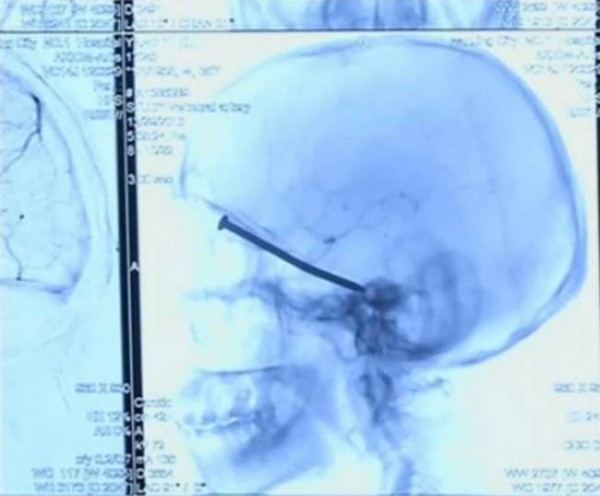

Yang yi Kui, un chinois de 55 ans originaire de la province de Jiangsu a ainsi survécu à un horrible accident. En effet, un clou avait pénétré l’orbite de son œil et s’était logé dans son crâne. L’accident est survenu le 29 décembre dernier, alors que Yang yi Kui utilisait une machine à découper pour effectuer quelques travaux dans sa maison.

Il explique que le clou, qui était resté coincé dans la machine, a volé lorsqu’il a démarré la machine et est venu se loger dans sa tête, en perforant sa peau. Se sentant défaillir, Yang Yi Kui est allé à l’hôpital où la radio faite sur place a permis aux docteurs de voir que le clou s’était enfoncé assez profondément dans son crâne.

Les chirurgiens ont procédé à une opération afin de lui enlever le clou de la tête avec une telle minutie que sa vision n’a pas du tout été affectée.